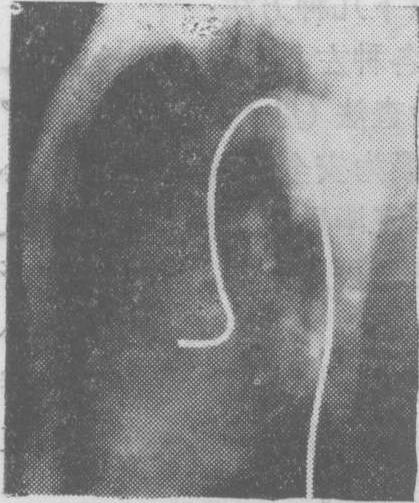

图3 猪尾状造影心导管

(2) 选择性左心室和主动脉造影: 选择性左心室造影可通过经胸壁穿刺左心室法、穿刺心房间隔左心导管检查法或经动脉逆行左心导管检查法(见“左心导管检查” 条) 等来施行。其中以后者最为安全可靠,并可同时施行选择性主动脉造影,尤以经皮肤穿刺股动脉法送入猪尾状左心室造影心导管最为简便(图3)。

术前准备除需作碘造影剂的过敏试验外,与经动脉逆行左心导管检查同。如从上肢动脉或颈外动脉送入心导管则以选用右侧较易送到升主动脉,如从下肢动脉送入心导管则选用左、右两侧股动脉均可。心导管顶端进入升主动脉后有时通过主动脉瓣有困难,此时顶端一段弯成圆圈状的心导管例如猪尾状心导管则较易送入。猪尾状心导管一般通过经皮股动脉穿刺法送入,当其套在导引钢丝外时,其顶端弯成圆圈部分即变直,便于经动脉穿刺口进入,撤出导引钢丝则顶端恢复圆圈状。当顶端经过主动脉瓣进入左心室有困难时,还可将导引钢丝再置入其管腔,但不到达顶端圆圈状部分,这样心导管的硬度加强而顶端仍呈圆圈状,更易于送入左心室。注射造影剂时心导管顶端的位置宜游离在心室腔中,并离二尖瓣较远,以避免造影剂注入心肌发生危险或反流入左心房,人为地造成二尖瓣关闭不全的假象。摄片取右或左前斜位投照。